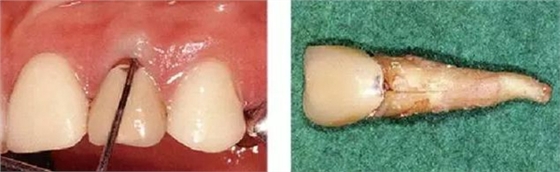

●外傷引起的附著喪失②

右上2修復(fù)物脫落而來(lái)院的患者(上圖是修復(fù)物臨時(shí)裝戴的照片)。頰側(cè)僅有一點(diǎn)有6mm的牙周袋。5個(gè)月前不存在此牙周袋。診斷為無(wú)法保存而進(jìn)行了拔牙。拔牙后,肉眼可清晰觀察到破折線。根據(jù)診查推斷為該深度牙周袋是由于牙根破折導(dǎo)致附著喪失,細(xì)菌沿著破折線進(jìn)入后破壞了牙周膜造成的。